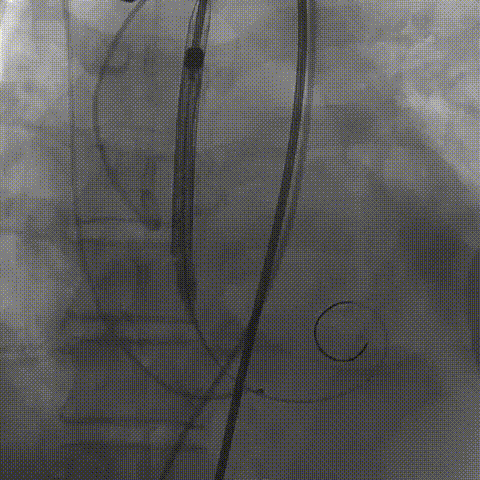

23mm球囊预扩,冠脉显影正常;输送器顺利过弓

初次释放,无冠窦畸形猪尾难以到达窦底,定位带来挑战;释放至工作位,瓣膜(AV29)位置偏低

瓣膜(AV29)完全回收后重新定位释放